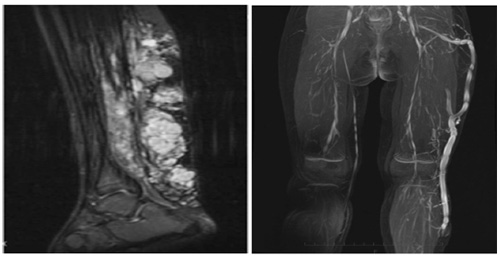

Chụp cộng hưởng từ nhằm nhận định quy mô của các đám dị dạng tĩnh mạch, nhận định các tổn thương xương, mô mềm và liên quan của chúng với những cấu trúc xung quanh như cơ, mỡ …

Chụp cắt lớp vi tính mạch máu có thể dựng lại mô hình 3D hệ mạch máu ở chân bệnh nhân, đặc biệt có giá trị để phát hiện các cục máu đông trong lòng mạch và sự thông nối giữa hệ thống động mạch và tĩnh mạch (thông động – tĩnh mạch).